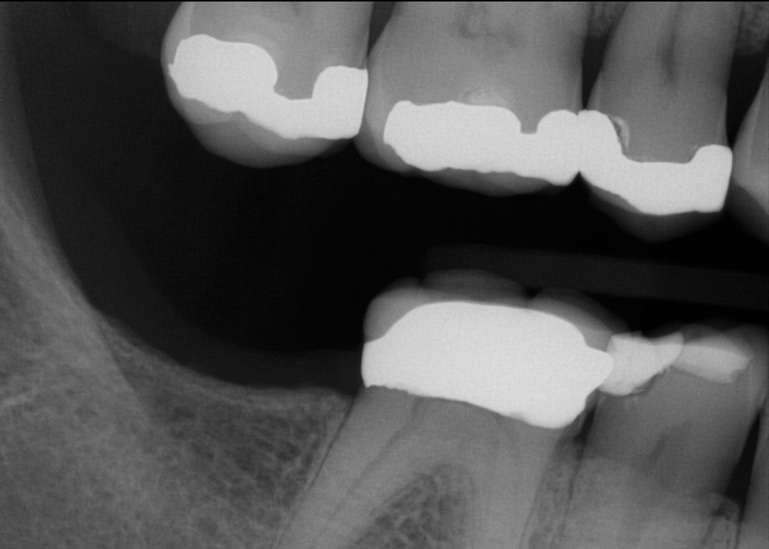

Fig 1. In 2009 patient No. 1 presented with a missing tooth at site No. 31.

Figure 1

Fig 2. In 2016 patient No. 1 manifested no alterations of tooth position No. 2.

Figure 2

Another consideration is mean vertical displacement of unhampered posterior teeth, which in some studies was minimal: 0.8 mm37 and 0.9 mm30 (Table 1). Yet, there could have been sites where the amount of extrusion was clinically relevant. When Lindskog-Stokland et al assessed the risk of over-eruption using 1 mm as a threshold, they stated there was an odds ratio of 3.3 that unimpeded molars would extrude 1 mm compared to opposed molars.30 Based on their calculations, however, it is unclear which patients with a missing molar are at risk of over-eruption (Figure 1 through Figure 4). Indeed, if susceptible individuals could be identified, then restorative therapy could be initiated to stabilize their occlusion (eg, tooth replacement). Furthermore, odds ratios can be highly misleading, and predictive values would provide clinicians a better perspective as to what percentage of sites may experience significant extrusion.41,42